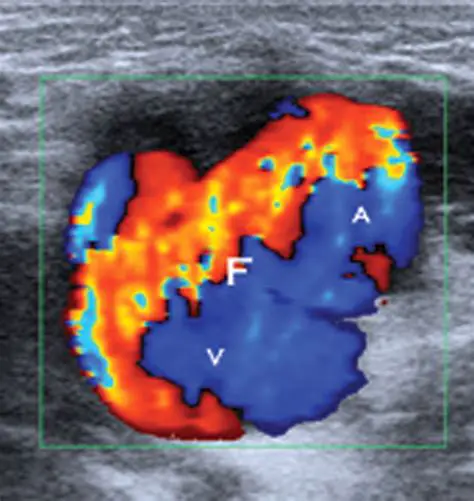

Spectral Doppler Waveform in Arteriovenous Fistulas